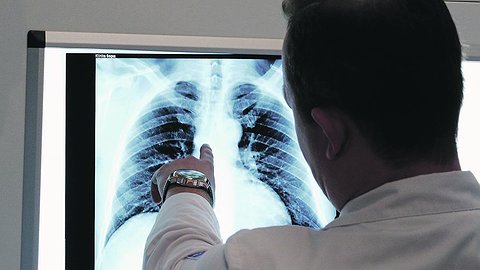

Коронавирус может проявить себя уже после выздоровления пациента, сообщили учёные из России и Японии. Отложенный эффект выражен поражением внутренних органов. Причём он возможен даже у людей, у которых не было явных симптомов пневмонии. Это происходит из-за того, что патоген атакует костный мозг, говорят специалисты. Именно поэтому в тканях различных органов патологоанатомы находят мегакариоциты - гигантские клетки костного мозга. Это объясняет и проблемы с тромбами у людей с тяжёлой формой COVID-19, и отмирание тканей органов, которое медики наблюдают при вскрытии тел погибших.

Специалисты департамента фундаментальной медицины Дальневосточного федерального университета (ДВФУ) вместе с учёными Тихоокеанского государственного медицинского университета и японскими коллегами исследовали биологические материалы более 100 пациентов, умерших от COVID-19, который был подтверждён ПЦР-тестом. Статья об этом опубликована в журнале Archiv EuroMedica. Группу контроля составили 14 пациентов, погибшие в результате травм, несовместимых с жизнью. Специалисты сделали вывод: SARS-CoV-2 может атаковать красный костный мозг.

- Вирус попадает на эпителий, где размножается, а потом выходит в кровь и атакует мишени, которыми может выступать как внутренний эпителий (ЖКТ, лёгкие, мочеполовая система), так и красные кровяные тельца - эритроциты, - рассказала "Известиям" руководитель исследования, профессор кафедры фундаментальной медицины Школы биомедицины ДВФУ Галина Рева. - Мы предполагаем, что главной целью вируса становится красный костный мозг, где он повреждает эндотелий, в норме регулирующий миграцию созревающих эритроцитов в кровь. Именно по этой причине с клетками иммунитета происходят странные вещи, а в тканях различных органов мы находим мегакариоциты - очень крупные клетки костного мозга.

Мегакариоциты в норме становятся источниками тромбоцитов, отвечающих за свёртываемость крови, но при COVID-19 они сгущают кровь в сосудах без необходимости, пояснила профессор. А погибшие эритроциты могут стать причиной поражения нейронов мозга, сосудов и внутренних органов, которым перестаёт хватать кислорода. В тяжёлых случаях возможна полиорганная недостаточность (отказ органов): человек фактически начинает задыхаться, а аппараты ИВЛ не помогают, поскольку кислород нечем транспортировать в ткани.

Фиброз лёгких - самое очевидное проявление COVID-19. Но формируется он не только из-за рубцевания в зоне повреждения, рассказала Галина Рева. Поскольку причиной фиброза становятся выброшенные в кровь мегакариоциты, аналогичные явления могут происходить в тканях всех паренхиматозных (плотных) органов - лёгких, печени, селезёнки, почек, поджелудочной и щитовидной желёз.